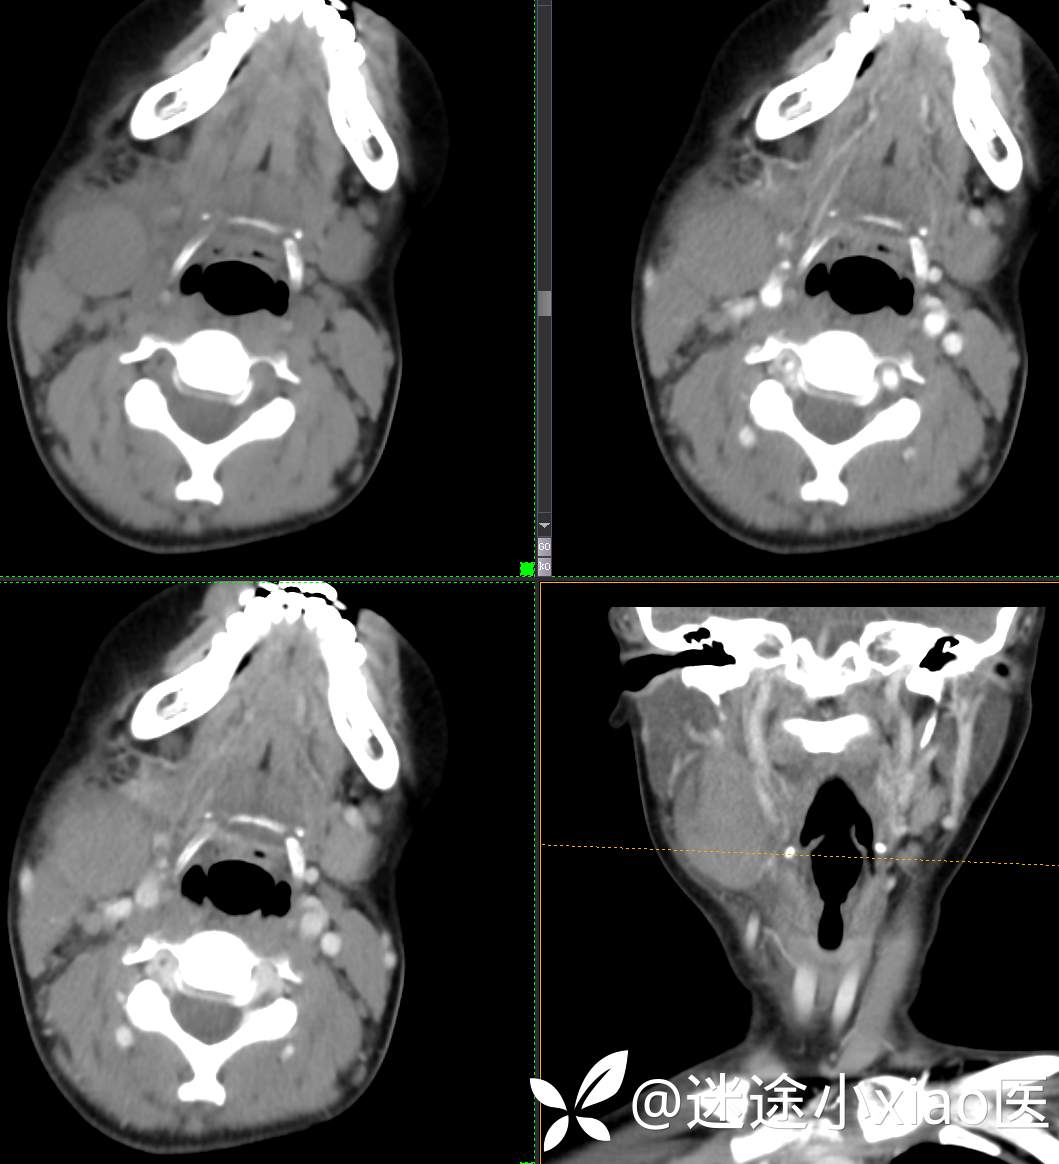

头颈组16:青少年女性,发现右颈部肿物半月余,感染?肿瘤?

现病史:患者半月余前无明显诱因下发现右颈部肿物,大小4.2*2.1cm,局部无红肿,皮温正常,有压痛,感头晕头痛,无其他不适。查甲状腺及颈部淋巴结B超提示:双侧甲状腺多发结节;右侧多发肿大淋巴结。初步诊断为“淋巴炎”,予“头孢类”抗生素抗感染治疗12天(具体药物不详),自觉肿块胀痛缓解,头晕头痛症状仍存。